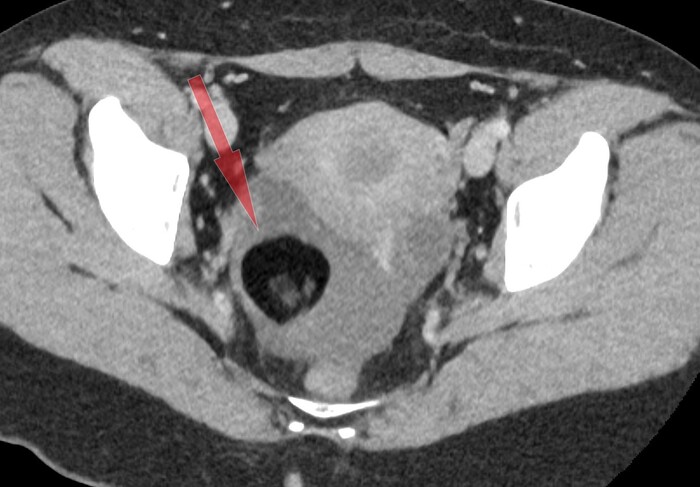

Однако в малом тазy, в области правого яичника было обнаружено округлое образование с чёткими контурами и размером 4 х 4 см, которое содержало преимущественно жир и некоторые плотные включения:

Дополнительно обращал на себя внимание геморрагический (с примесями крови) выпот в дугласовом пространстве:

Со средней плотностью 29 HU (вода 0 HU- +10 HU, жир -200 HU - 0 HU, вода с примесями крови - выше +20 HU):

С определением типа образования правого яичника проблем особых не было: так выглядит классическая зрелая тератома на КТ.

Проблема была больше в выпоте с кровью в малом тазу, т.к. это не нормально (у женщин детородного возраста допускается некоторое количество свободной жидкости в малом тазу, но в совсем небольших и без значительных примесей крови), а значит тут, скорее всего, имеется острая патология, и скорее всего правого яичника в виде перекрута оного вокруг своей оси на фоне тератомы. При повторной оценке корональных срез было локализовано место перекрута (симптом "водоворота" сверху от правого яичника):